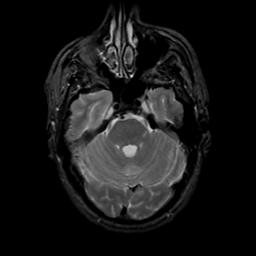

MR Study #16, June 23, 1991 -- Slice #14

[Home][Help][Clinical][Tour 1][Tour 2] Slice 14